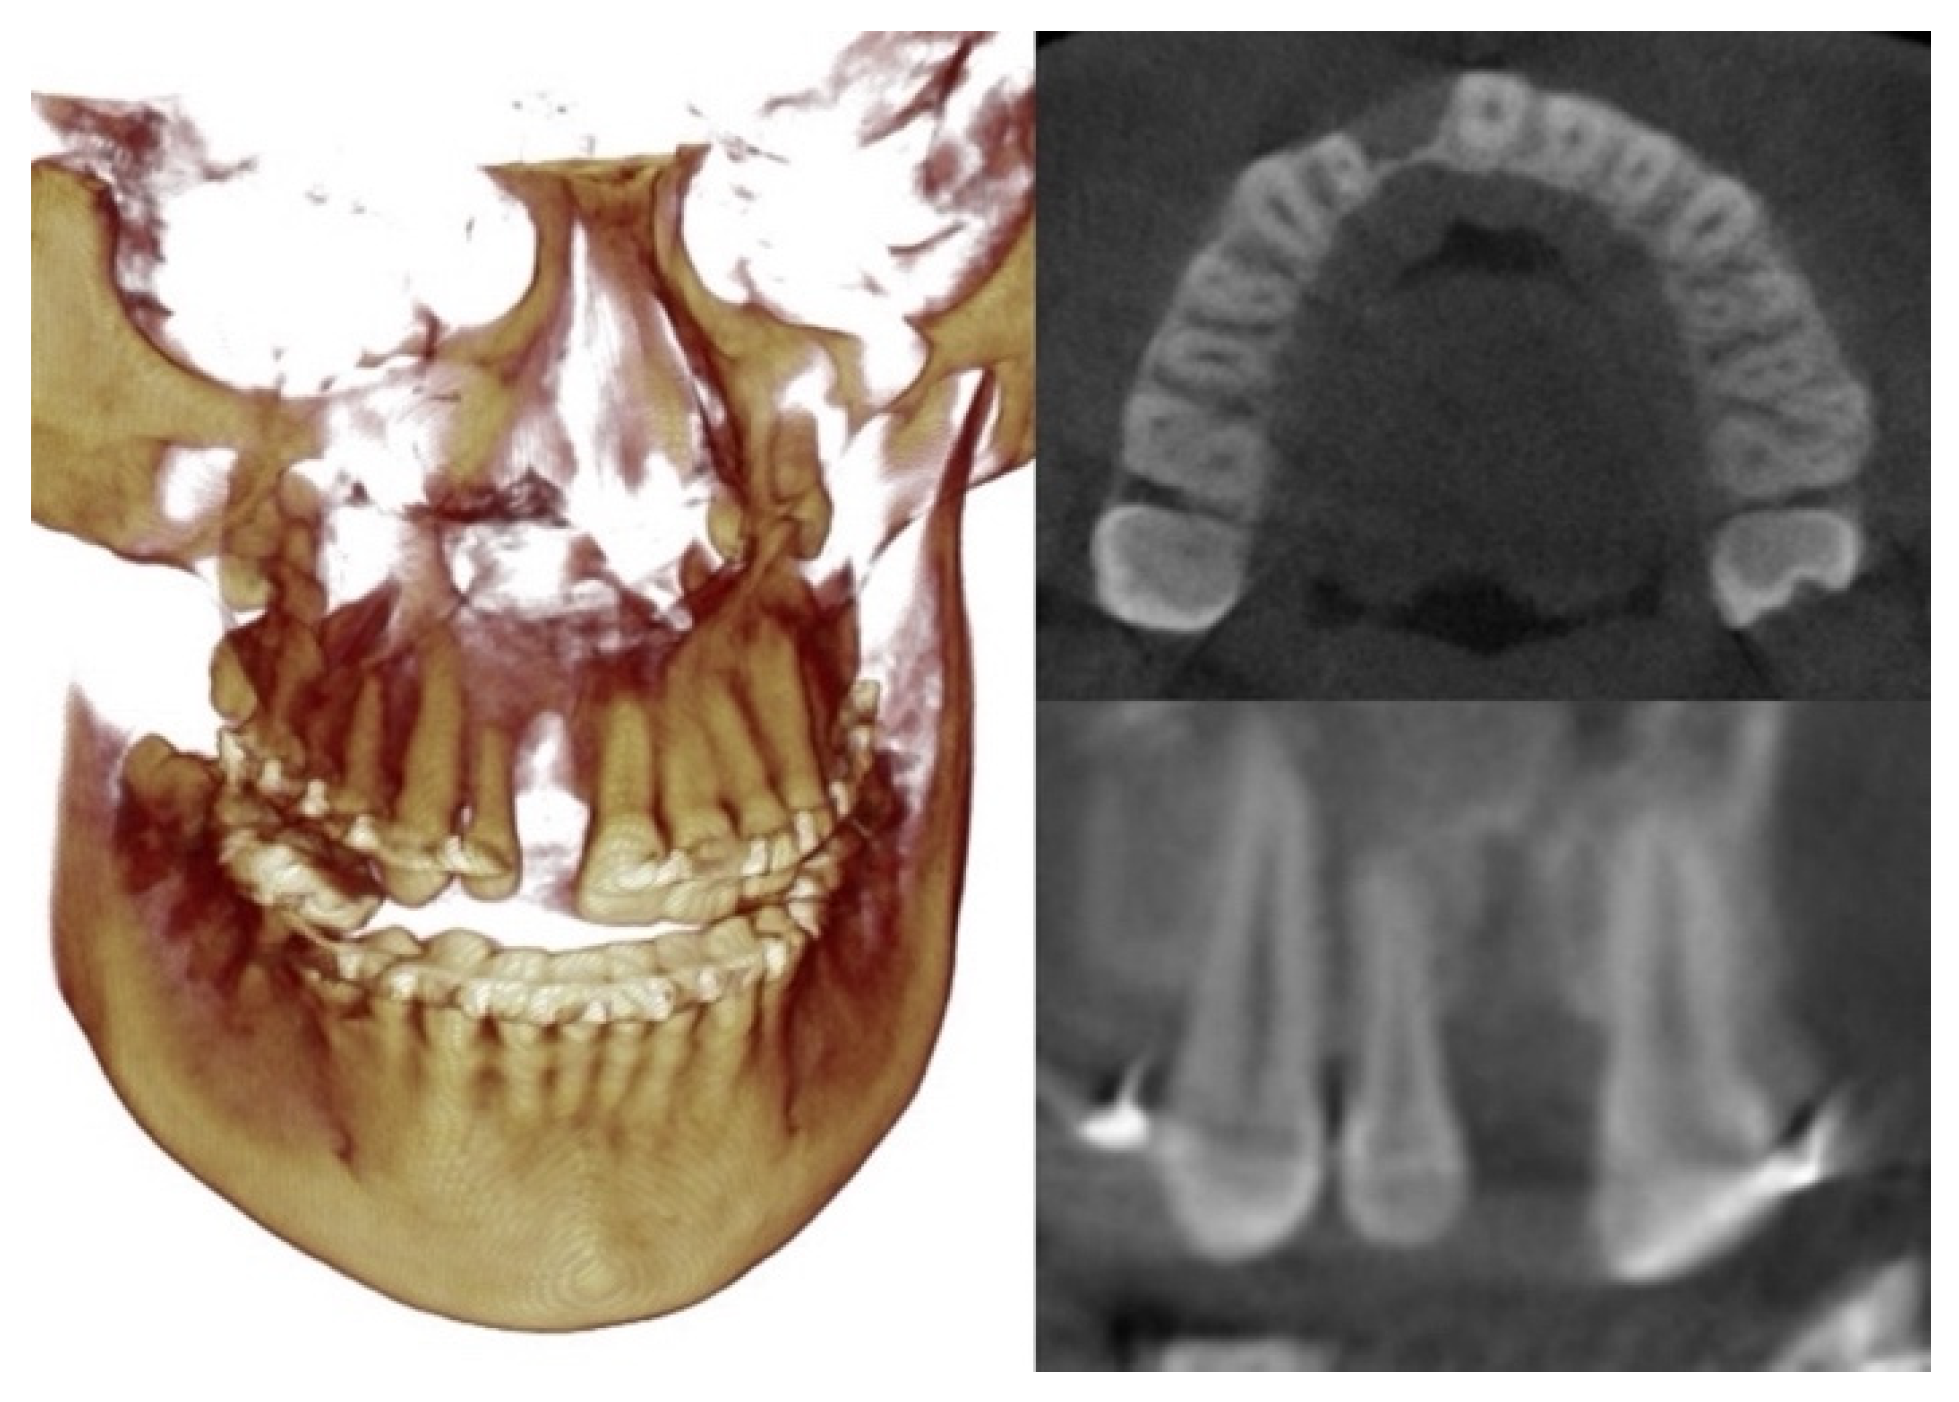

2. Case Description